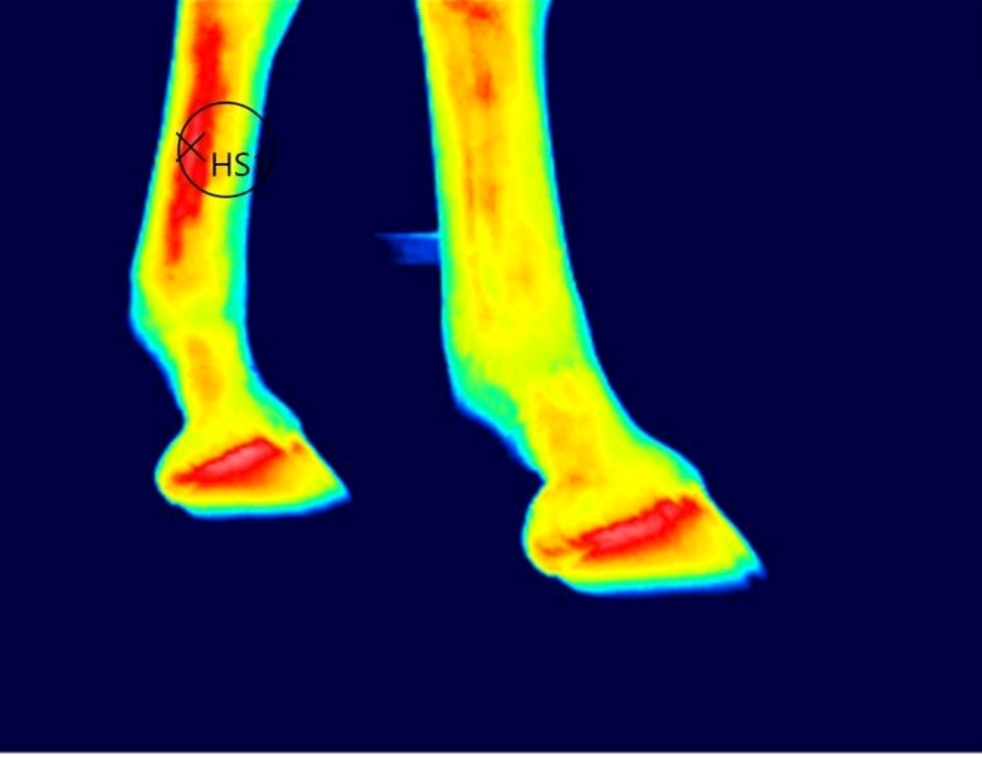

Thermografie ist die bildliche Darstellung der Temperaturverteilung an der Oberfläche eines "festen" Körpers. Man kann also die Temperatur an der

Oberfläche darstellen aber nicht in Objekte hineinschauen. Sie dient der Eingrenzung der tiermedizinischen Diagnostik, Trainingskontrolle, Auswirkung von Narben und Verletzungen, Überprüfung von Ausrüstung, Wirkung von Therapien und Therapiegeräten

Sie hat keine Nebenwirkungen und ist stressfrei für das Pferd. Durch eine Thermografie werden schulmedizinische Maßnahmen reduziert, da die Bereiche für

Diagnostik eingegrenzt werden. Teilweise werden Auffälligkeiten bereits vor Auftreten von Symptomen sichtbar in der Thermografie.

jedes Bild wird nachbearbeitet und bezeichnet. Es werden Markierungen wie z.B. Hotspots gesetzt. Der Kunde erhält einen Bericht mit den auffälligen Bildern